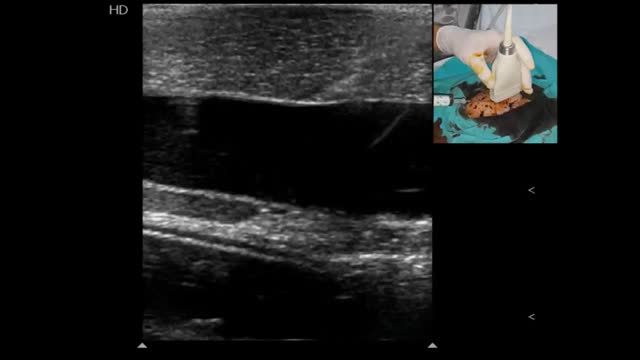

Confirming proper vessel cannulationAlong with detecting direct and indirect signs of vessel cannulation and observing blood returning, it is recommended to have the guidewires shown into the target vessel when used2,7 (Video 7). This practice allows to finally advance the catheter into the target vessel and not in adjacent tissues if it is unintentionally placed in a wrong position. The final position of the catheter should also be directly and indirectly displayed (Video 8).2,7 In peripheral venous cannulation, an agitated saline flush (10ml) passed through the catheter allows to display microbubbles running into the vessel and thus guaranteeing its adequate position and function7 (Video 8). For central venous cannulation, an agitated saline flush is injected through the catheter, normally observing the microbubbles flowing in the right atrium7 within 1–2s16 in simultaneous echocardiographic assessment in subcostal or apical 4-chamber views, performed with a phased-array or a convex probe.

Ultrasound-guided vascular cannulation: the procedure itselfStatic vs real-time techniquesOnce a target vessel is selected, cannulation can be executed using an static technique (US-guided vascular location and skin marking but without using real-time US guidance) (Video 1) or using a dynamic or real-time technique, consisting in observing the screen for direct or indirect signs of the needle entering into the vessel.2,7 (Videos 2, 3 and 4). Both US techniques are more successful for cannulation in comparison with the landmark technique.2,7 When comparing the static and dynamic techniques, the latter has demonstrated a better performance for vascular cannulation compared to the former.2,7 Advantages of the static technique is that it does not require sterile covers for the probe or a needle-screen coordination by the operators. On the other hand, in the real-time technique, cable and probe protection (as well as using sterile US gel) is needed to maintain a sterile technique, the latter usually resulting in some loss of resolution. Additionally, dynamic techniques require a perfect coordination between needle insertion, screen observation and the evaluation of blood returning from the needle, skills that necessarily require proper training and learning curve.

Evaluating the lung sliding before and after cannulating these vessels is recommended, since it allows to quickly detect the presence of pneumothorax.7,16